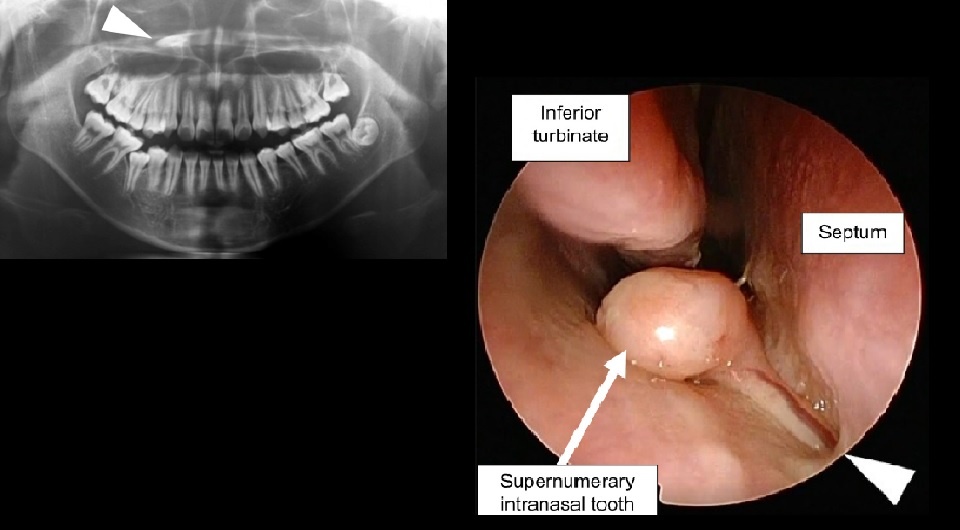

Японские хирурги удалили ребенку зуб из носа

Umezawa et. al / BMJ Case Reports, 2025

Японские стоматологи описали случай формирования зуба в носовой полости ребенка. Зуб нашли при рутинном обследовании и он не причинял беспокойства, но чтобы избежать воспаления в будущем, хирурги удалили его через нос под общим наркозом. Случай, который описан в BMJ Case Reports, редкий не только из-за того, что зуб располагался в носу, но еще и потому, что он никак не был связан с верхней челюстью, а был прикреплен к носовой перегородке в виде полипа.

Химико Умедзава (Himiko Umezawa) из больницы Сайсекай Йокохамаши Нанбу с коллегами описал случай возникновения у ребенка интраназального зуба. Мальчика младшего школьного возраста привели в отделение стоматологии по поводу нарушения прикуса, а когда ему сделали рутинную ортопантомографию, то обнаружили похожее на зуб образование в правой носовой полости. Мальчик при этом не жаловался и свободно дышал носом. Визуальный осмотр оториноларинголога не выявил никаких патологий, а стоматолог подтвердил нарушение прикуса, но все остальные коренные зубы были на своих местах.

На компьютерной томографии был виден зуб, повернутый коронкой к глоточной стороне основания полости носа. При этом зуб находился в носу без контакта с верхнечелюстной костью. По КТ мальчику поставили диагноз дополнительного интраназального зуба и запланировали оперативное вмешательство.

Хирурги удалили зуб эндоскопически через носовую полость под общим наркозом. Оказалось, что он был прикреплен к носовой перегородке в виде полипа. Зуб был полностью сформирован и в длину достигал 15 миллиметров. За пациентом наблюдали в течение месяца после операции — никаких осложнений у мальчика не возникло.

Точная причина возникновения эктопических зубов неизвестна. Авторы работы считают, что такое происходит из-за чрезмерной активации зубной пластинки, при этом зачаток зуба отделяется от основной части пластинки и мигрирует в носовую полость. В данном клиническом случае интересно еще и то, что зуб никак не был связан с костью, а располагался в виде полипа носовой полости.